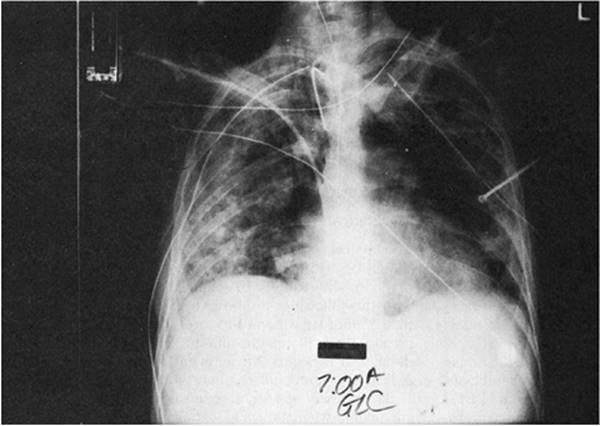

Figure 136.2. Diffuse interstitial and panacinar infiltrates are seen in a 36-year-old patient with acute respiratory distress syndrome. Also notice one of the complications of the respiratory support—a right mainstem intubation.

The changes seen on the chest radiograph in ARDS are characteristic but nonspecific, rarely revealing the etiology of the syndrome. Acutely, pulmonary edema is seen. Interstitial infiltrates progress to a diffuse, fluffy, panacinar pattern (Fig. 136.2). Although it may be difficult to differentiate from cardiogenic pulmonary edema, there is generally an absence of pulmonary vascular redistribution, pleural effusion, or cardiomegaly. The panacinar infiltrates may consolidate and, with time, take on a patchy or nodular pattern. If the patient improves, radiographic results may revert to normal. If the disorder progresses, a pattern of diffuse interstitial fibrosis may ensue (Fig. 136.3).

Therapeutic interventions may alter the radiographic findings. Pulmonary infiltrates may increase with injudicious fluid administration. Positive pressure ventilation and PEEP may lead to hyperinflation, and subcutaneous, mediastinal, retroperitoneal, and intraperitoneal emphysema, or pneumothorax. Mainstem bronchus intubation may lead to ipsilateral pneumothorax or contralateral lung collapse (Fig. 136.4).